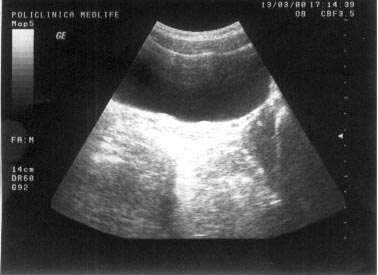

Imaginea hiperecogena

Atunci cand reflectarea ultrasunetelor este foarte intensa, pe ecran nuantele de culoare vor fi aproape de alb. Exprimarea semiologica va fi corespunzatoare unei structuri accentuat ecogene sau hiperecogene. Imaginea hiperecogena este data de bogatia continutului in tesut fibros, conjunctiv si grasime a structurii respective.

Exemple:

structuri dense, dure, impenetrabile pentru fasciculul ultrasonor care va fi in intregime reflectat (calculi);

steatoza hepatica;

hemangiomul hepatic

Figura 5. Hemangiom hepatic lobul stang

Figura 6. Hemangiom renal - la nivelul treimii medii a

rinichiului drept, mica zona hiperecogena, rotunda, care deformeaza conturul

renal.